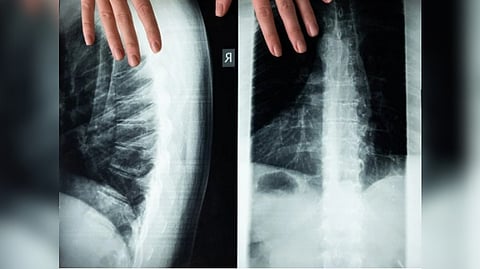

BIRMINGHAM: According to the University of Birmingham, scientists discovered that blocking the inflammatory response in the spinal cord may reduce damage after spinal cord injury.